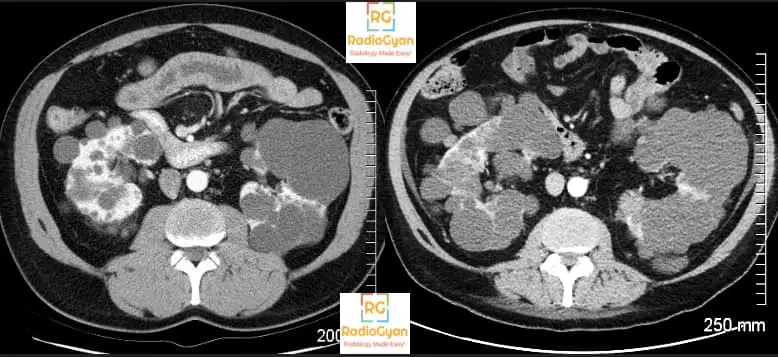

- Renal cysts are formed in uteri and grow with age. Up to a certain extent the renal function is preserved but in the latter phases, the cysts compress the renal parenchyma and renal insufficiency sets in. Have a look at the serial images of a patient with ADPKD a few years apart. There is progressive thinning of normal renal parenchyma on the image on the right.

- The predictive power of total renal volume has found to be better than age, genotype, serum creatinine, BUN, urinary albumin, or monocyte chemotactic protein-1 levels.

- Non contrast CT is the imaging modality of choice.

- Volume can be calculated by

- Ellipsoid formula:

- Length x breadth x-height x 0.52.

- Not very accurate but provides a rough estimate.

- Height corrected Total renal volume = Renal volume/ height in meters

- A height-corrected total kidney volume (htTKV) of 600 ml/m predicts the future development of CKD stage 3 within 8 years.

- A recent study also observed that in patients with TKV > 1500 cm3, eGFR reduced at the rate of 4.3 ml/min/year.